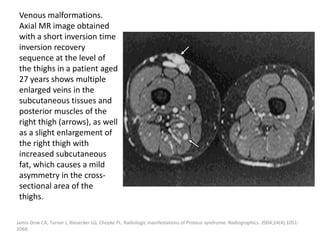

functional impairment and contracture.

The clinical and imaging features can be

confusing and often overlap with those of

other vascular malformations and tumors.

The gastrocnemius muscle is the most

commonly affected muscle in FAVA.

Amarneh M, Shaikh R. Clinical and imaging features in fibro-adipose vascular anomaly (FAVA). Pediatr Radiol. 2020;50(3):380-387.

De Crée C (2015) Rupture of the Medial Head of the Gastrocnemius Muscle in Late-Career and Former Elite Jūdōka: A Case Report.